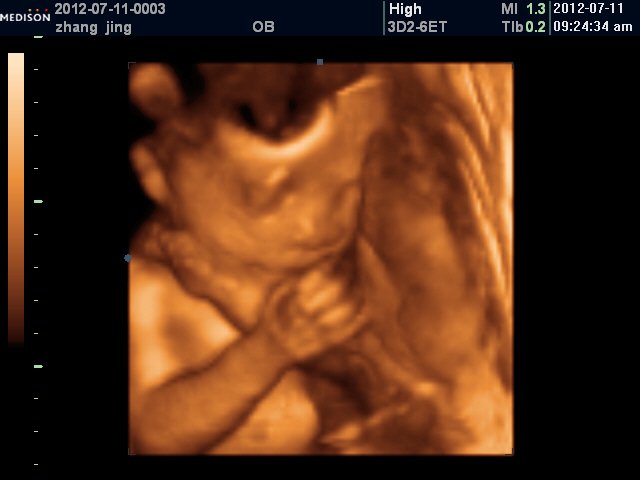

患者信息:女 28岁 陕西 西安 病情描述(发病时间、主要症状等):具体的:左侧脑室后角1.2cm, 右侧未探及, 羊水最大深度7.8cm,羊水指数24.4cm,双顶径6.9cm,下肢可显示,脊柱连续想得到怎样的帮助:是不是胎儿有问题啊?说什么可能脑积水,脊柱裂,……记不得了,让过个月去再查4维。有没有什么更好的办法赶紧检查出来呢?曾经治疗情况及是否有过敏、遗传病史:无遗传史,有点贫血